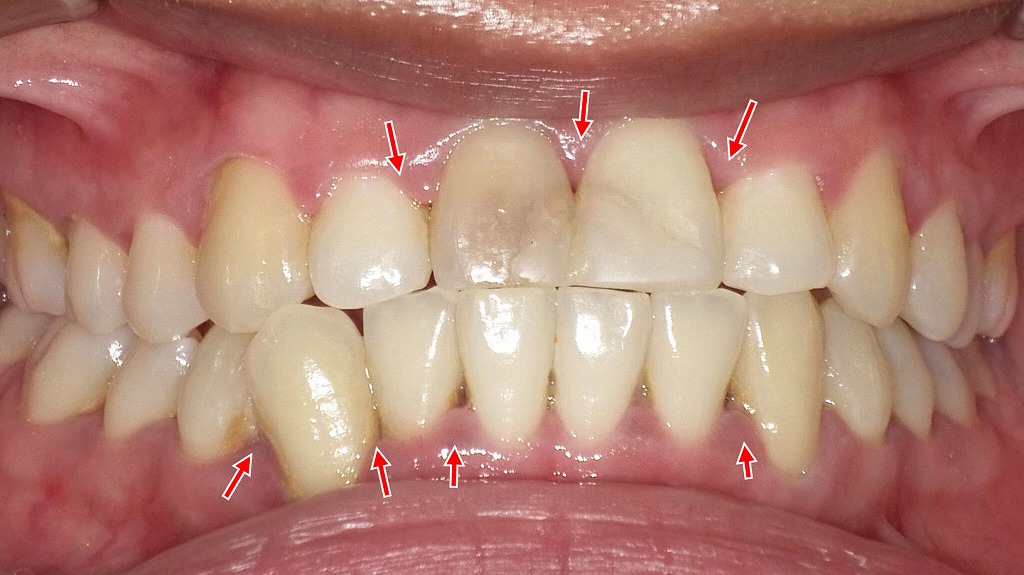

むずむず・かゆい違和感は歯ぐきのSOS|プラークが引き起こす歯肉炎

この画像では、赤い矢印で示されている部分に歯ぐきの発赤(赤み)・腫れ・軽度の出血が確認できます。これらは典型的な**歯肉炎(歯ぐきの炎症)**の所見です。

✔ プラークが炎症の主な原因

歯の付け根に溜まった**プラーク(細菌の塊)**が、歯ぐきを刺激して炎症を起こしています。プラークが溜まると、以下のような症状が出やすくなります。

- 歯がむずむずする

- 歯ぐきがかゆい・違和感がある

- ブラッシング時に少し血が出る

- 歯ぐきが赤く腫れる

✔ むずむず感は「軽い炎症のサイン」

この段階では痛みがはっきり出ないため、患者さんは「むずむずする」「気持ち悪い」といった違和感で気づくことが多いです。これは、歯肉の浅い部分に炎症が起きている典型的な状態です。

✔ 放置すると歯周病へ進行

歯肉炎はこの段階で改善すれば治りますが、放置すると歯周病へ移行し、

・歯ぐきが下がる

・歯がぐらつく

・口臭が強くなる

など、より深刻な症状へつながります。